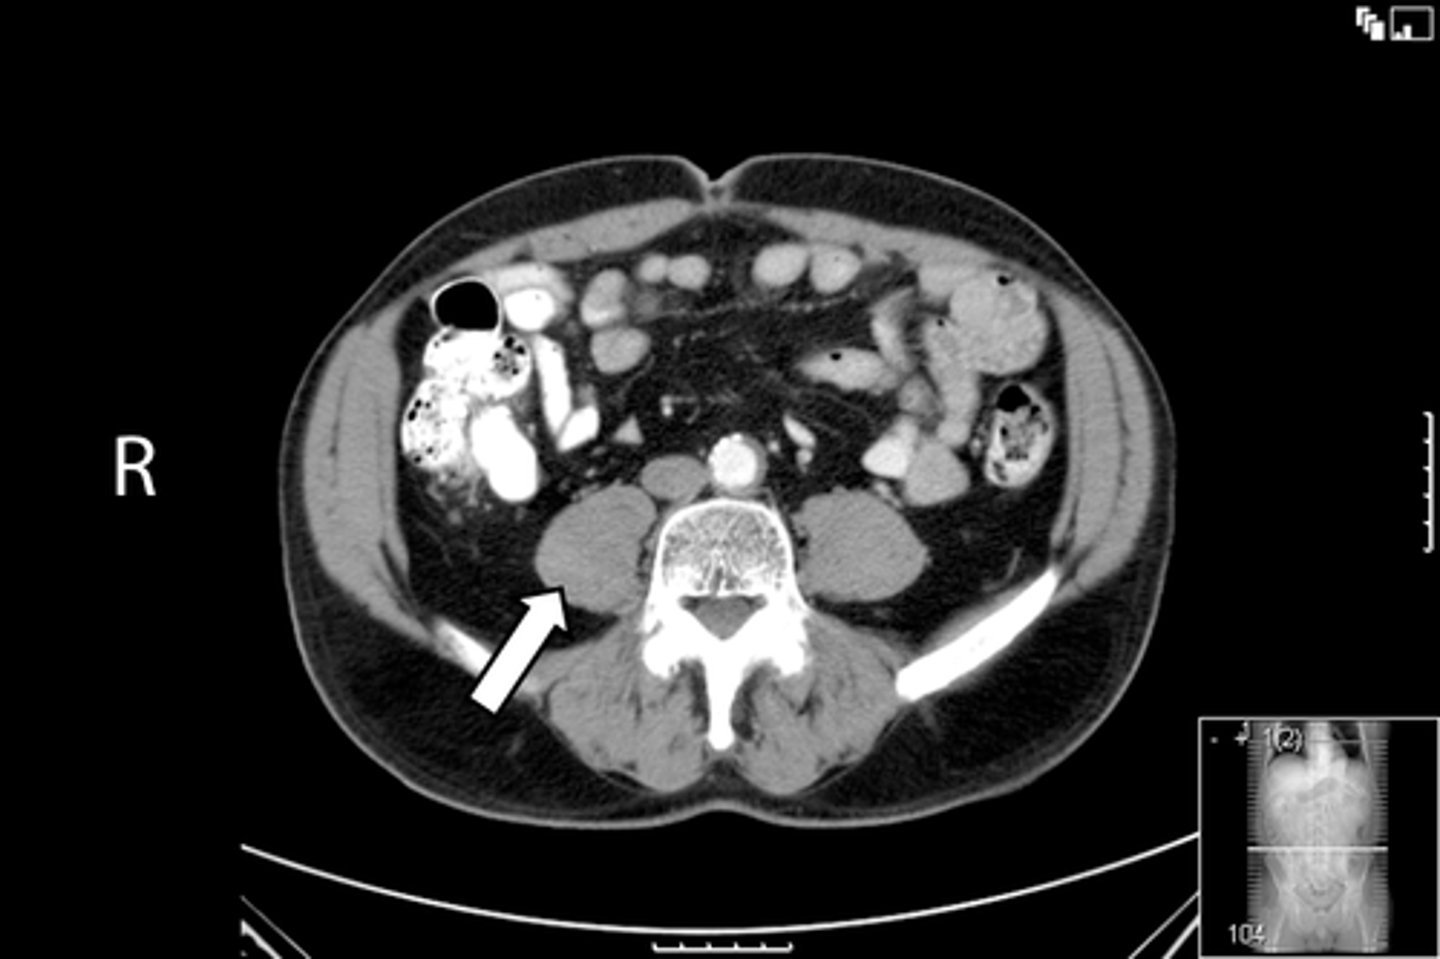

Axial male pelvis CT

What is the image?

<p>What is the image?</p>

New cards

Aorta

What is indicated in the image?

56

Cecum

<p>What is indicated in the image?</p>

IVC

58

L ilium

L psoas muscle

60

R ilium

R psoas muscle

62

R rectus abdominis

Terminal ilium